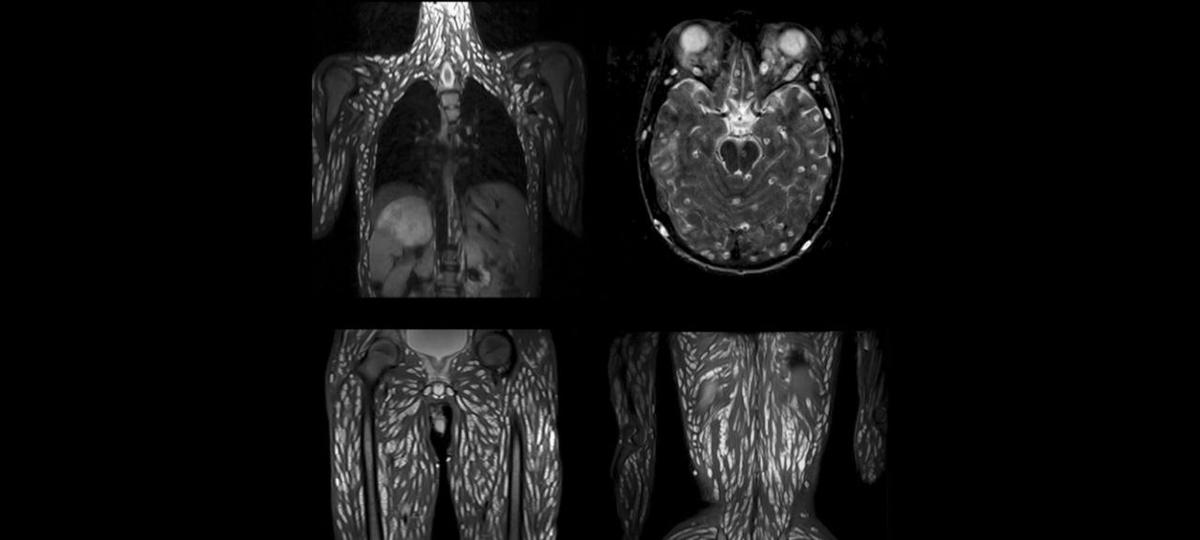

На снимках КТ такие случаи выглядят пугающе: десятки застывших кальцифицированных точек — это те самые паразиты, которые обосновались в теле надолго.

• Заражение: Личинки паразитов сначала поселились в кишечнике.

• Миграция: Затем они начали путешествовать по всему телу, проникая в мышцы, мягкие ткани и области вокруг суставов.

• Маскировка: В тканях личинки превращались в плотные кальцифицированные капсулы, годами оставаясь незамеченными и медленно разрушая организм изнутри.